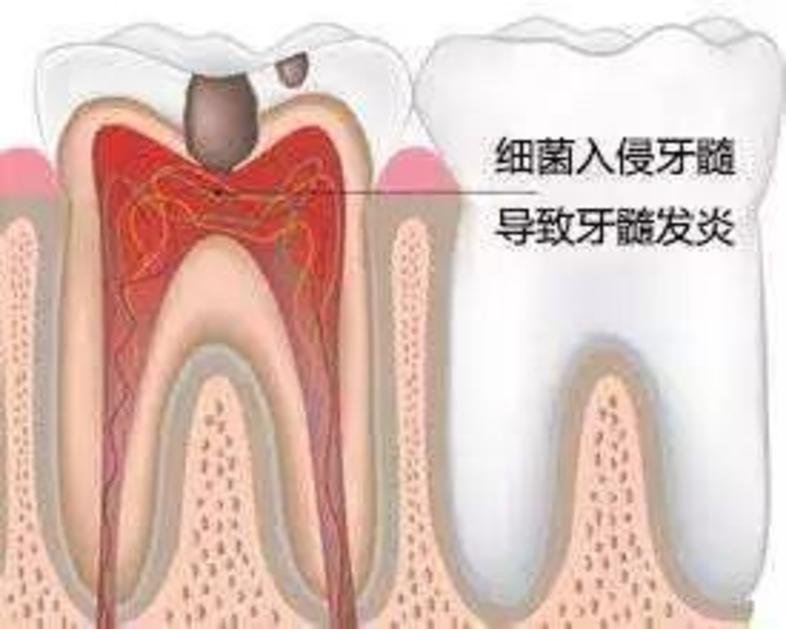

牙髓炎:细菌进入牙神经,患者会有剧烈的疼痛感。如果不及时治疗,细菌会杀死牙神经

龋病可发展为牙髓炎、根尖周炎,引起剧烈疼痛,严重者还可造成间隙感染